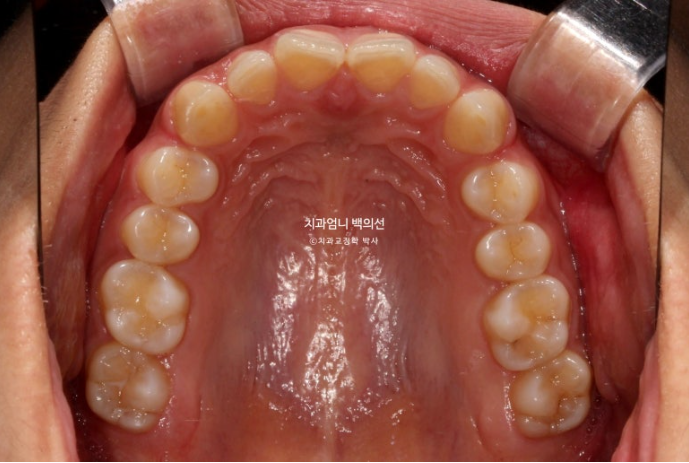

중간에 잇몸성형도 했습니다. 치아를 과도하게 덮고 있는 잇몸을 걷어내는 과정입니다.

24년 9월부터 25년 1월까지, 5개월간 14개 추가장치를 모두 낀 후 모습입니다.

총 치료기간은 10개월 입니다.

25.01

길이가 짧아 답답해보이던 앞니가 잇몸성형으로 비율이 좋아지며 보기에 시원해졌습니다.

좋았던 교합은 잘 유지되었고

10개월의 치료기간 동안 치근흡수는 없으며 치근평행도는 양호합니다.

아래앞니과 위 앞니의 상당량의 함입이 눈에 띕니다. 위아래 앞니가 2mm씩 함입되었습니다.

덕분에 입술은 처음보다 좀 더 편하게 다물리게 되었습니다.